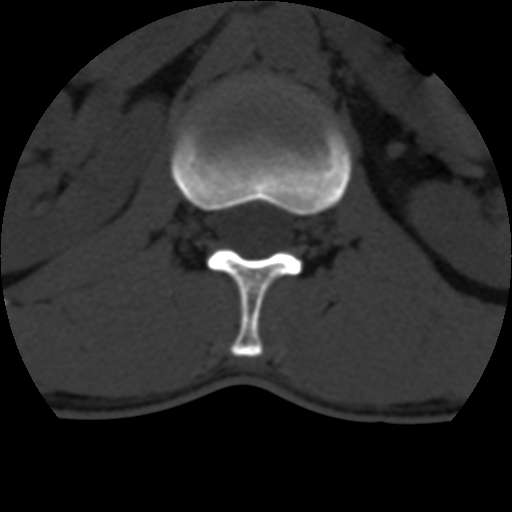

男,31岁,从6米高处坠落伤两天,腰背部疼痛,临床要求ct扫描胸10-腰1。请大家帮忙看看骨质有问题吗?

t12、l1锥体前缘轻度楔形变,平扫示椎体前缘骨小梁欠规整,第9幅图示椎体前缘骨质不连续,结合外伤史考虑椎体轻度压缩骨折。

楼主扫描层厚可能较大,每个椎体只有三个层面.

从所示层面分析,无明确骨折征象,象类似病人我个人会建议mri除外骨挫伤.

从上查骨窗第九片椎体前缘皮质显示断裂.压缩骨折?